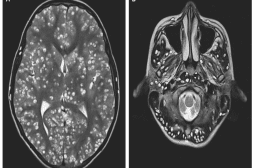

LES MALADIES

J'AI MAL

J ai Mal Bras et mains Bras et mains Tête et cou Torse et haut du dos Jambes et pied